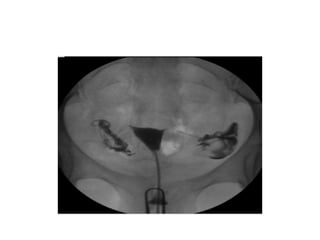

• HSG Findings in genital tube

-lead pipe appearance

-beaded appearance

-tobacco pouch appearance

-golf stick appearance

-cotton wool appearance

-cobble stone appearance

Cloudy sign

tobacco pouch appearence

• Broad filling defect, smooth regular outline:

polyp/fibroid

• Multiple irregular filling defects (moth eaten

appearance)- uterine adhesions-ashermans

syndrome

• HSG Findingsin genital tube -lead pipe appearance -beaded appearance -tobacco pouch appearance -golf stick appearance -cotton wool appearance -cobble stone appearance

• Broad fillingdefect, smooth regular outline: polyp/fibroid • Multiple irregular filling defects (moth eaten appearance)- uterine adhesions-ashermans syndrome